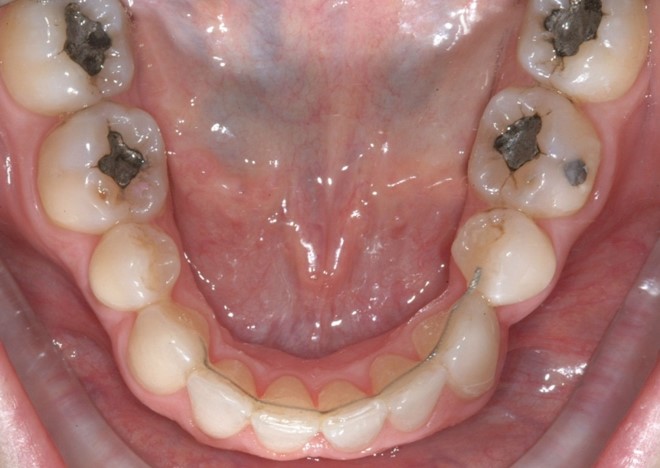

Il protocollo terapeutico ha previsto l’estrazione del primo premolare inferiore sinistro (3.4) e del primo superiore destro (1.4), l’applicazione di una apparecchiatura fissa linguale 2D e di una meccanica asimmetrica di ancoraggio e movimento ortodontico a entrambe le arcate (Figure 3a-b).

Per la chiusura dello spazio all’arcata inferiore, dopo la preliminare fase di allineamento e livellamento2, con la stessa sequenza iniziale di archi (.014” e poi .016” Nichel-Titanio), è stato temporaneamente applicato un sistema di ancoraggio ausiliario vestibolare, mediante fibre rinforzate, bondate sulla superficie vestibolare di 3.5, 3.6, 3.7 (Figura 4).

Successivamente, per controllare il movimento radicolare distale del canino inferiore sinistro (3.3), è stato applicato un sistema di forze che ha sfruttato: la forza singola distalizzante e di chiusura spazi data dalla catenella elastica con ruolo stabilizzante anche verticale su 3.3, inserita e agganciata in due segmenti, uno mesiale e uno distale, nelle rispettive alette dello slot occlusale del 3.3, e una coppia di forze di uprighting data dall’arco ortodontico .016” Nichel Titanio; quest’ultimo è stato inserito distalmente nello slot ausiliario dell’attacco linguale sul 3.5 ottenuto ripiegando verso occlusale la terza aletta gengivale, e poi nel tubo singolo sul 3.6, e mesialmente, da mesiale verso distale e da gengivale verso occlusale nello slot di 3.3, generando una flessione verticale di secondo ordine, la cui rotazione in senso linguale veniva controllata dalla catenella elastica stessa in appoggio su di esso. Il segmento di arco distale a 3.2 è stato ripiegato in senso gengivo-vestibolare (Figura 5).

Nota tecnica: una volta ottenuto il corretto posizionamento del 3.3, al fine di simmetrizzare l’arcata inferiore e centrare le linee di simmetria, è stata applicata una molla ad anse aperte tra 4.4 e 4.3 su arco .016” in acciaio (Figura 6).